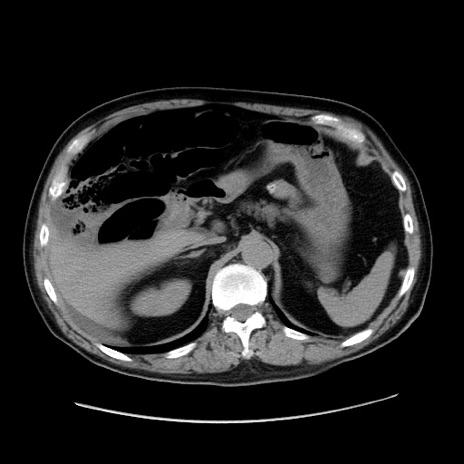

症例30(横断像)

【症例】80歳代男性

【主訴】臍周囲痛

【現病歴】約6時間前から臍下部痛が出現。次第に腹部膨隆・背部痛も生じてきたため来院。背部痛の場所は変化しない。

【身体所見】意識清明、BT 36.3℃、BP  131/87mmHg、P 87bpm、SpO2 100%(RA)、臍周囲自発痛・圧痛あり、反跳痛なし、自発痛部位に一致して板状硬あり、腹部膨隆、腸雑音減弱、CVA tenderness両側陰性。

【データ】WBC 19600、CRP 0.33